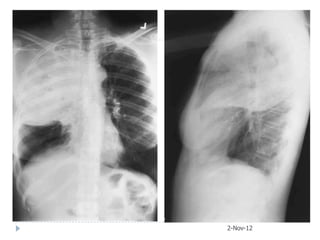

1: 15.09.2008 2: 20.09.2008

2-Nov-12

3: 12.10.2008

4: 22.10.2008